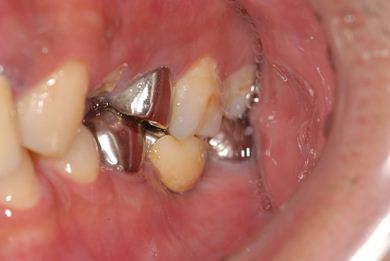

抜歯即日スピードインプラント治療

| 主訴 | 前歯が折れていてないので、インプラント治療を希望。 | ||||||||||||||||||||||||||||||||

| 治療内容 | インプラント1本(抜歯即日スピードインプラント)、ハイブリッドセラミッククラウン1本 | ||||||||||||||||||||||||||||||||